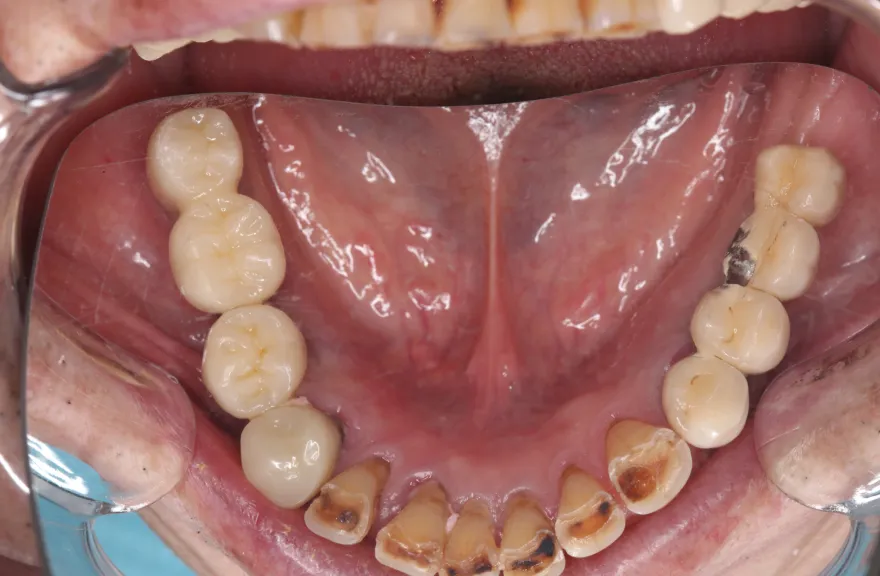

【治療例 5】上の歯がグラグラで困っている 62歳

- 相談内容

- 数年前に全体的に治療したが、上のつながっている歯がグラグラして噛めないということで来院されました。

- 治療費用・方針

-

上顎は5本の歯を保険のブリッジ治療で連結してある状態でした。どの歯の状態も良くなく、今回なんとか治療を行ったとしても近いうちに再びトラブルを起こしてくることが予想されました。

下顎は9本の歯が残っており、虫歯はあるものの差し歯として使える状況でした。

しかし、患者さんとの話し合いの中で、「数年前に行った治療なのに再び全てやりかえないといけないのは単純にしんどい。もうやりかえのないようにしたい」という患者さんの強い思いが伝わってきました。

今回で完全に治療をやり切ってしまい、今後は最小限の介入で歯科と付き合えるよう、上下顎残っている歯の全ての抜歯、必要な本数のインプラント埋入、上顎は総義歯形態で対応することとしました。 - 治療のリスク